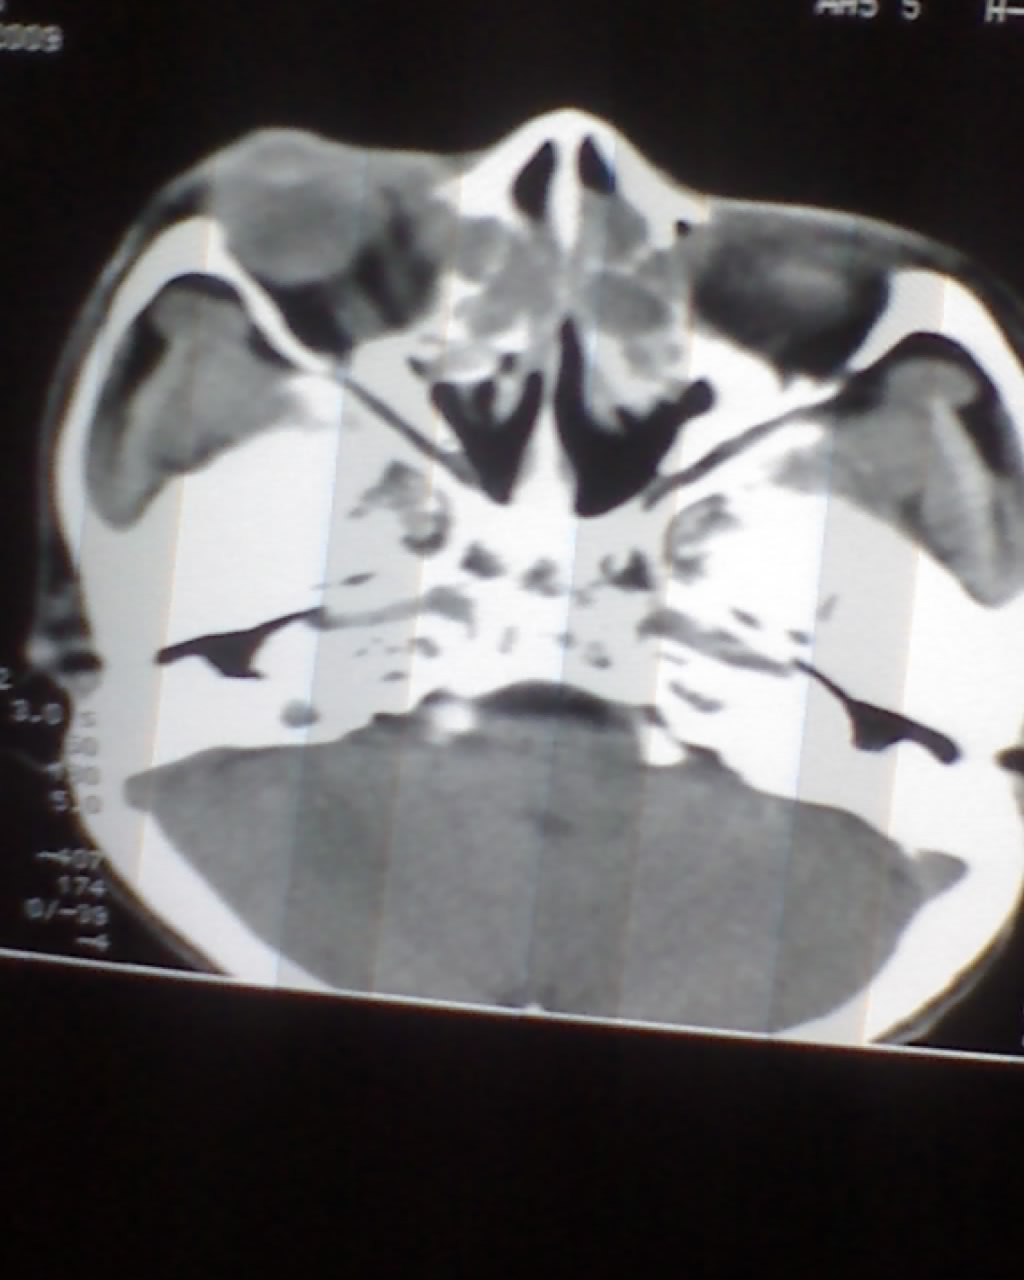

女,45岁,右眼突出,视力模糊来诊。

双侧筛窦可见软组织影充填,筛板破坏,肿块突向双侧眼眶内,以右侧为明显,右侧眼球向前外推压,右视神经稍外移。

双侧额窦,筛窦可见软组织影充填,筛板破坏,肿块突向双侧眼眶内,以右侧为明显,右侧眼球向前外推压,右视神经稍外移。